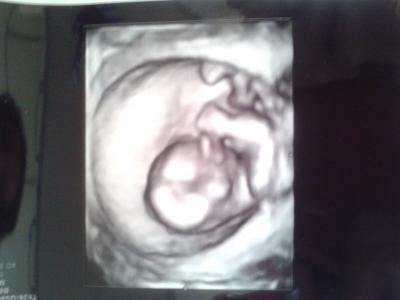

So heute war endlich wieder der ersehnte Termin und es ist zum Glück alles okay.Oh man warum hat man jedes mal immer so eine Angst das was nicht stimmen könnte? Sie wollte sich zwar noch nicht festlegen aber sie tippt mal auf ein Mädchen. Lg

Bild zu Fa Termin - Forum für April - Mamis

Oh, was für ein schönes Bild!! Da hat Deine FÄ ja ein gutes Gerät! Schön, dass alles in Ordnung ist :) Die Sorgen und das Bangen lässt wohl leider so schnell nicht nach. Aber wir machen das schon!!!